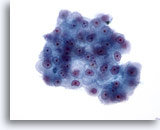

画像 3

肝FNA – 良性肝細胞

核はわずかに大小不同であり、反応性変化を来した肝細胞に典型的な低N/C比を示します。微小な細胞質空胞および細胞質内色素がみられます。

60倍

画像 3

肝FNA – 良性肝細胞

核はわずかに大小不同であり、反応性変化を来した肝細胞に典型的な低N/C比を示します。微小な細胞質空胞および細胞質内色素がみられます。

60倍